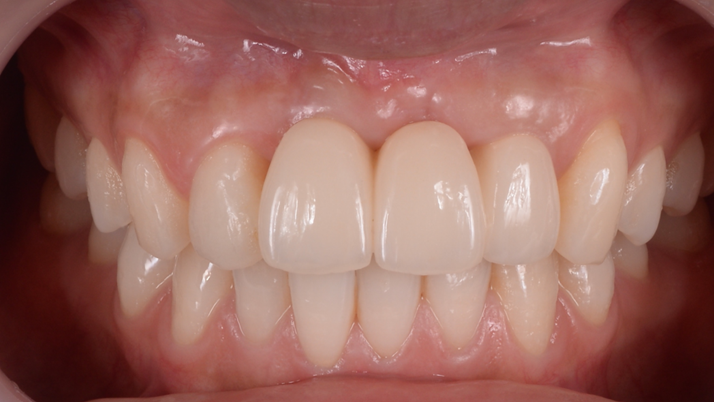

Clinical case: BPET PREDICTABILITY - State-of-the-Art SOCKET SHIELD

- Courtesy of Dr. Howard Gluckman, South Africa -

“AnyRidge is perfect for the anterior esthetic zone due to its strong initial stability & fast osseointegration.

Plus, KnifeThread® ensures space maintenance when using the PET/Socket Shield/Root Membrane Technique, showing excellent bone growth.”